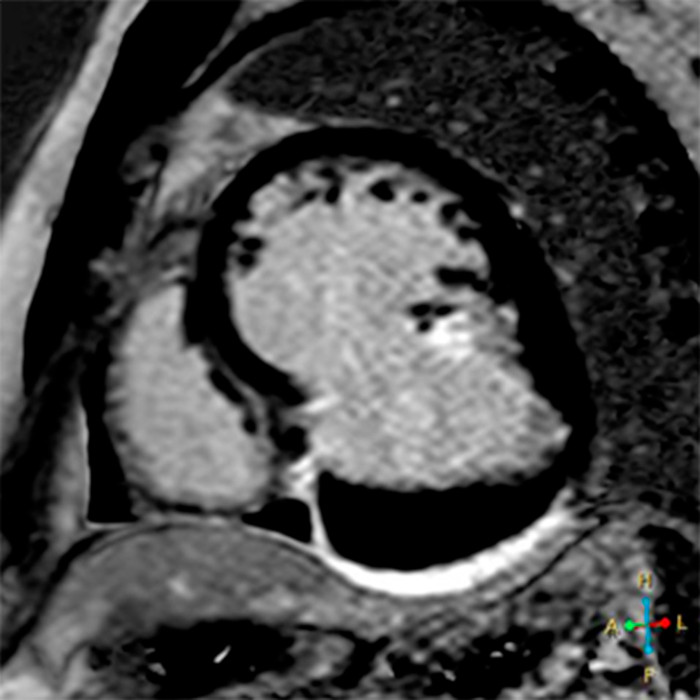

Se presenta el caso de un paciente de sexo masculino, de 50 años de edad, derivado por infarto agudo de miocardio de cara inferior, 25 días previos a la consulta, no habiendo sido revascularizado. Se encontraba clínicamente estable. Debido a presentar mala ventana acústica, se solicita la realización de una resonancia magnética cardíaca con contraste no ferromagnético (gadoterato de meglumina). Bajo esta técnica, se observa una cavidad en comunicación con la cámara ventricular izquierda, de cuello ancho y la presencia en su interior de un trombo que tapiza su superficie (Fig. 1, dos cámaras y Fig. 2, eje corto). Tras la administración del contraste, se observa realce tardío a los 10 minutos de la pared de esta estructura (Fig. 3, eje corto), certificando la naturaleza aneurismática y descartando el pseudoaneurisma ventricular. Debido a su tamaño, ante la posibilidad de desarrollo de falla cardíaca o evento embólico, se decide su intervención quirúrgica para plástica ventricular certificando la anatomía patológica la naturaleza fibrótica de su pared.